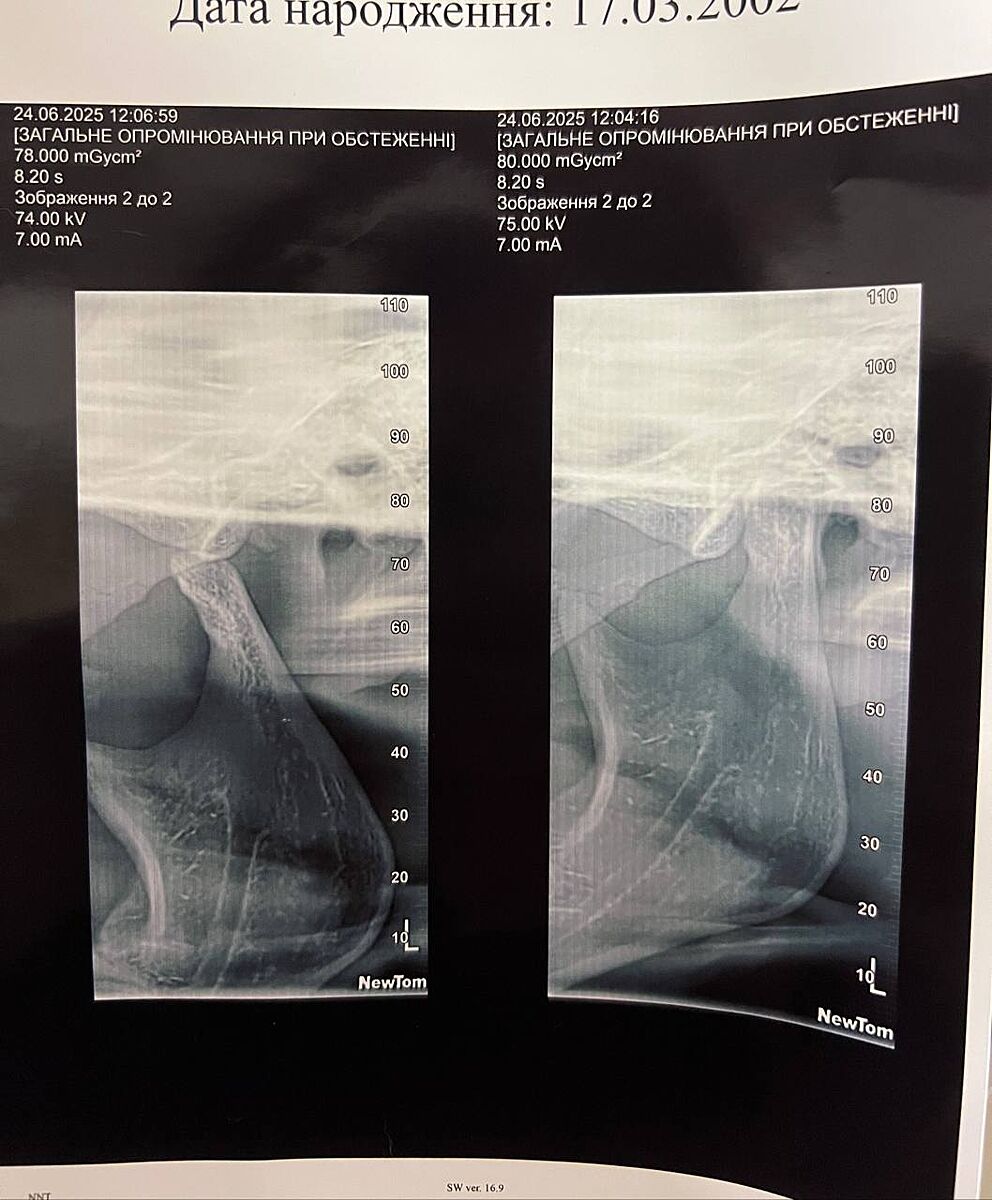

А можете ещё снимки глянуть пожалуйста

attached-photo

Как-то снимок несколько противоречит описанию узи, насчет движения головки внчс правой стороны - здесь наоборот гипермобильность, подвывих или привычный вывих сустава